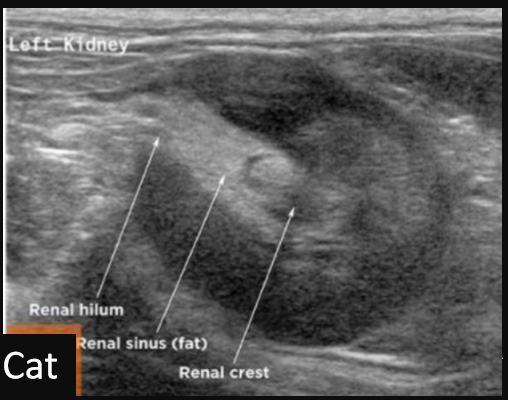

11

Q

Label this transverse view kidney ultrasound

A